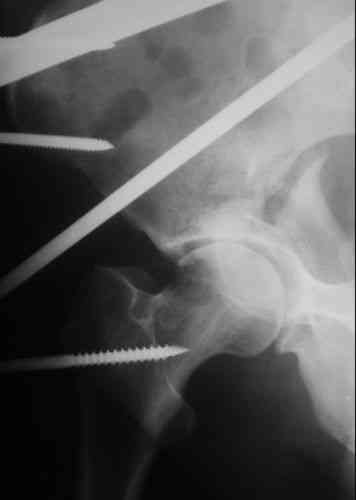

Пациентка 38 лет. В результате ДТП 02.09.06 получила поперечный перелом правой вертлужной впадины, центральный вывих правого бедра, разрыв правого крестцово-подвздошного сустава.

В одной из районных больниц вывих устранен, наложена система вытяжения по оси бедра и за вертельную область. Спустя 2 недели выполнен ВЧКО модулем "таз-бедро". Учитывая возраст пациентки и остаточный диастаз в области свода вертлужной впадины предполагается демонтаж аппарата, открытая репозиция и внутренний МОС вертлужной впадины через внутритазовый доступ.

На показанных снимках повреждение правого КПС не очень заметно...

У меня создалось впечатление( одна из РГ), что участок суставной поверхности нагрузочной зоны вертлужной впадины вдавлен( постарайтесь сделать КТ). Если это подтвердиться, то из внутритазового доступа отрепонировать будет невозможно.